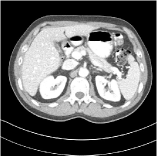

We have conducted experiments on 20 test slices (slice 20, slice 50, slice 100, slice 150 and slice 200 of patient L067, L143, L192, L310) of the Mayo Clinic data. Table I shows the averaged image quality of 20 test images with different methods. From Table I, we observe that Parallel SUPER significantly improves the image quality compared with the standalone methods. It also achieves 1.8 HU better average RMSE compared with Serial SUPER while its SSIM is comparable with Serial SUPER. Fig. 3 shows the reconstructions of L067 (slice 50) and L310 (slice 150) using PWLS-ULTRA, FBPConvNet, serial SUPER (FBPConvNet + PWLS-ULTRA), and parallel SUPER (FBPConvNet + PWLS-ULTRA), along with the references (ground truth). The Parallel SUPER scheme achieved the lowest RMSE and the zoom-in areas show that Parallel SUPER can reconstruct image details better.